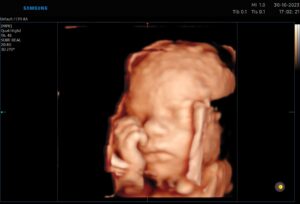

Morfologia de trimestrul II este una dintre cele mai spectaculoase ecografii. In cadrul acesteia evaluam cu foarte mare atentie dezvoltarea fiecarui organ in parte al bebelusului, si efectuam o serie de masuratori astfel incat sa verificam corespondenta cu normogramele international. Adica, verificam daca bebelusul se dezvolta armonios sau nu.

De asemeni, acesta este momentul optim pentru o fotografie memorabilia 3D sau live 4D cu zambetul bebelusului in burtica.

Intervalul de efectuare 22 de saptamani-24 de saptamani